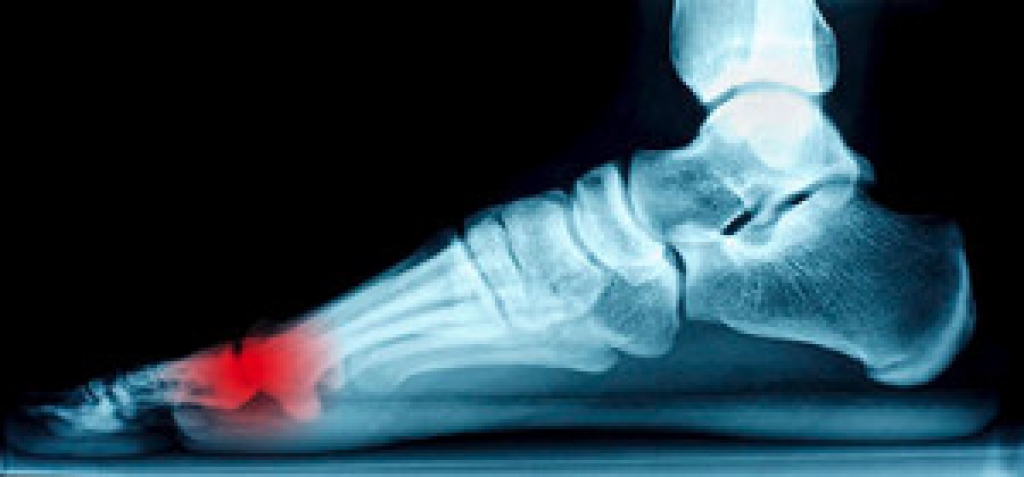

The Achilles tendon is a tendon that connects the lower leg muscles and calf to the heel of the foot. It is the strongest tendon in the human body and is essential for making movement possible. Because this tendon is such an integral part of the body, any injuries to it can create immense difficulties and should immediately be presented to a doctor.

There are various types of injuries that can affect the Achilles tendon. The two most common injuries are Achilles tendinitis and ruptures of the tendon.

- Extreme pain and swelling in the foot

Achilles tendon injuries are diagnosed by a thorough physical evaluation, which can include an MRI. Treatment involves rest, physical therapy, and in some cases, surgery. However, various preventative measures can be taken to avoid these injuries, such as: